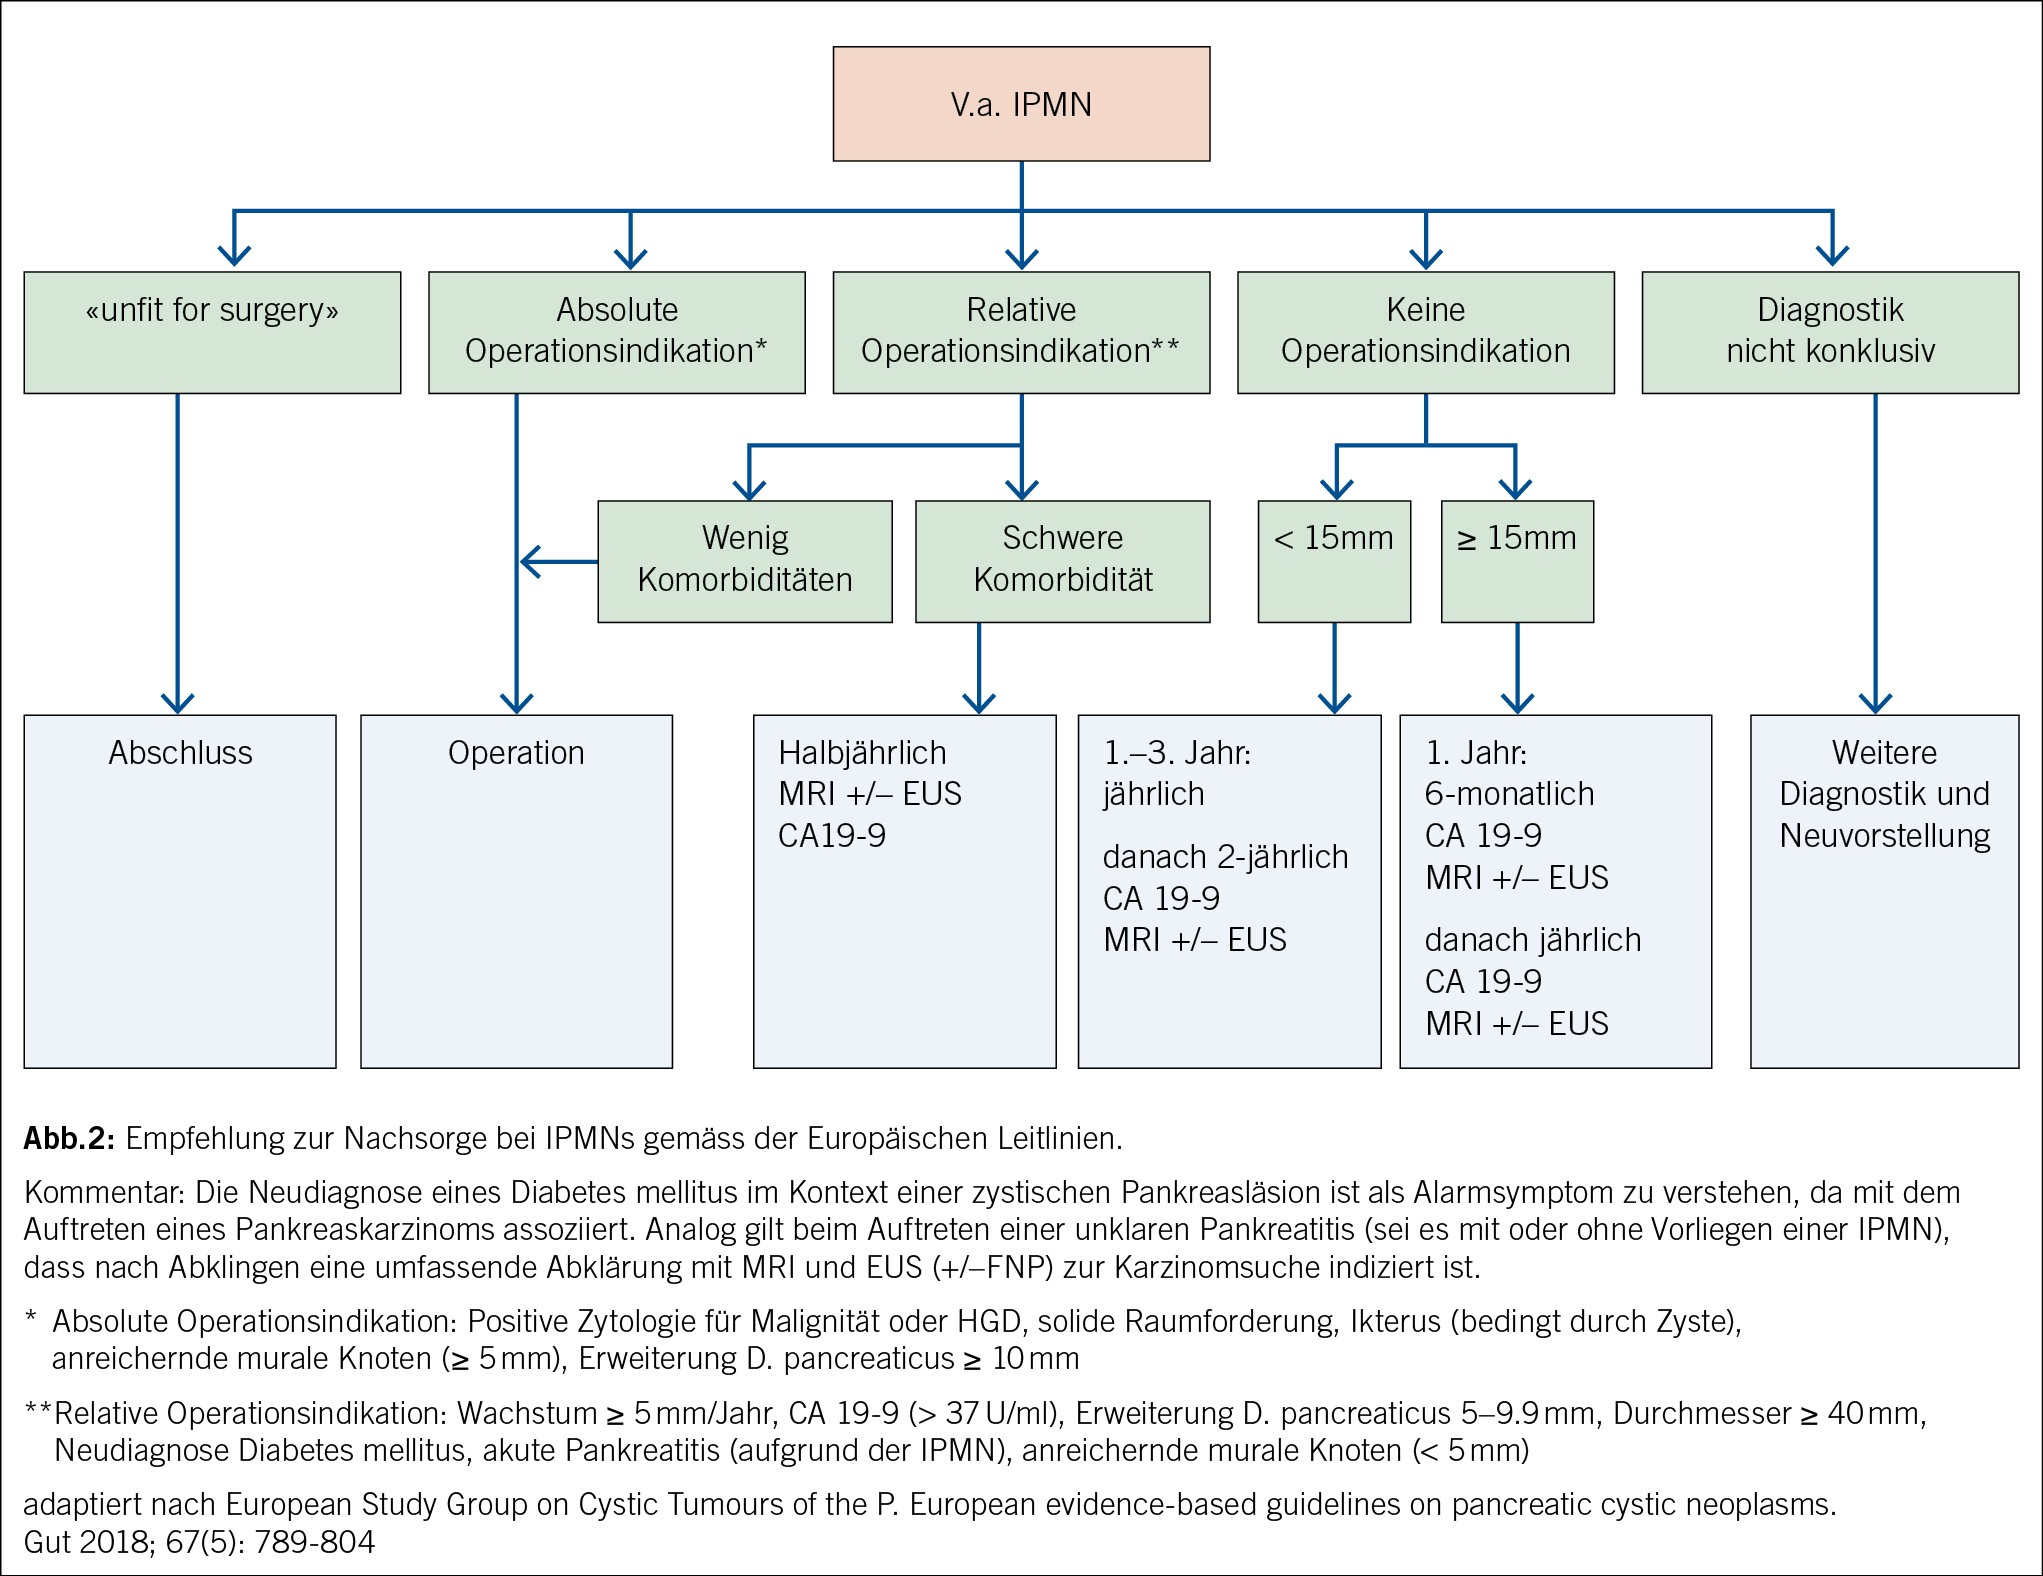

Die Duodenoskopie mit echter Seitblickoptik beurteilt die Papille. Eine sogenannte Fischmaulpapille (Abb. 3) ist pathognomonisch für eine Hauptast-IPMN und führt direkt zur Diskussion der chirurgischen Resektion.